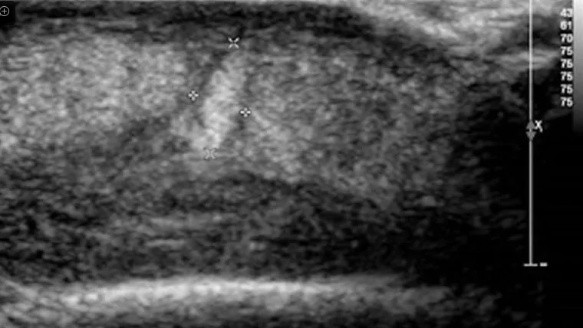

La señora fue a urgencias y allí descubrieron que del bulto principal salía un gusano. Tras una ecografía, hallaron una segunda larva viviendo en su rostro, que tuvo que ser extraída quirúrgicamente.